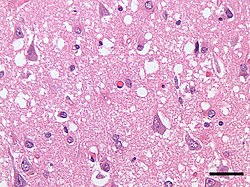

Prion xəstəliklərinin patomorfologiyası mikroskopik olaraq 4 yerə bölünür:

• Süngərvari dəyişikliklər.

• Neyronlarin itirilməsi

• Astrositoz

• Amiloid ərpin əmələ gəlməsi

Makroskopik olaraq isə beyin kütləsinin əhəmiyyətsiz dərəcədə azalmasi müşahidə olunur. TSE mikroskopik əsasinda boz maddə neyronlarının çıxıntılarında vakuollaşma, astroqlioz (astrositoz) və beyində aqreqatların çökməsi, mielinsizləşmə durur. PrP-nin neyronal itirilməsi sinir toxumasının apaptozu (hüceyrənin proqramlaşdırılmış ölümü) ilə nəticələnir. Bu da MSS-nin funksiyalarin pozulmasına gətirib çixarir. Mikroskopla baxdıqda coxlu oval vakuollar görünür.(1–50 mkm ölçüdə). Onlar ayrı-ayrı və qrup halında ola bilər. Parafinli toxumanın kəsiyində mikroskopik olaraq boşluqlar görünür. Hemotoksilin-eozinlə rəngləndikdə isə kiçik dənələr formasında görünə bilir. Prion xəstəlikləri zamanı beyində əsas zədələnən hissə qabiq nahiyyəni 3–4-cü qati olur. Adi halda onlar eozonofil dairələr formasında görünür. Bəzən onurağa beynində də motoneyronlarin azalması da müşahidə olunur.